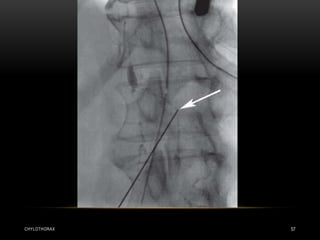

• Today there are several radiological treatments that can be used

in both traumatic and non-traumatic chylothorax .

• Much more experience is available for percutaneous

embolization of the thoracic duct , which can be performed as

an alternative to thoracic duct ligation and can be performed in

both adults and children .

• Embolization has a much higher success rate: if the thoracic

duct can be intubated successfully, the procedure is successful

in well over 90% of cases

CHYLOTHORAX 54

INTERVENTIONAL RADIOLOGY CHYLOTHORAX 53 •Today there are several radiological treatments that can be used in both traumatic and non-traumatic chylothorax . • Much more experience is available for percutaneous embolization of the thoracic duct , which can be performed as an alternative to thoracic duct ligation and can be performed in both adults and children . • Embolization has a much higher success rate: if the thoracic duct can be intubated successfully, the procedure is successful in well over 90% of cases